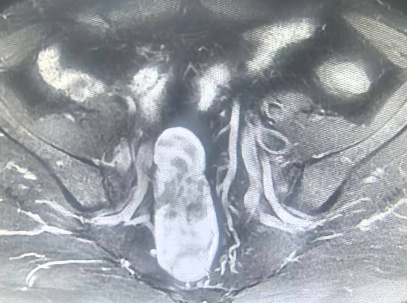

腹膜后间隙是人体深部的隐蔽区域,密布着腹主动脉、髂血管、输尿管、腹腔神经丛等重要脏器与神经,被称为外科手术的“高危地带”。此次就诊的50岁患者,因下腹部间断不适,排便次数增多,在当地医院行CT示盆腔占位,慕名来我院就诊。王志东教授团队接诊后,做好充分的术前准备,术前研读影像学资料,精准研判肿瘤浸润范围与解剖关系,找到肿瘤供血血管、避开周围脏器等潜在风险,制定了个性化腹腔镜微创切除方案。

手术当天,麻醉团队实施全麻后,王志东教授手术团队凭借丰富的腔镜操作经验,通过腹部数个“钥匙孔”大小的微小切口建立操作通道,借助腹腔镜高清放大视野,清晰呈现肿瘤与周围血管、输尿管的毗邻关系,用“抽丝剥茧”般的精细手法,运用最新的电外科器械,逐步分离肿瘤滋养血管,精准结扎、剥离,全程规避重要脏器与神经,精准夹闭肿瘤供血血管,有效控制术中出血。经过数小时的精准操作,最终将巨大肿瘤完整切除,术后恢复良好,顺利出院。